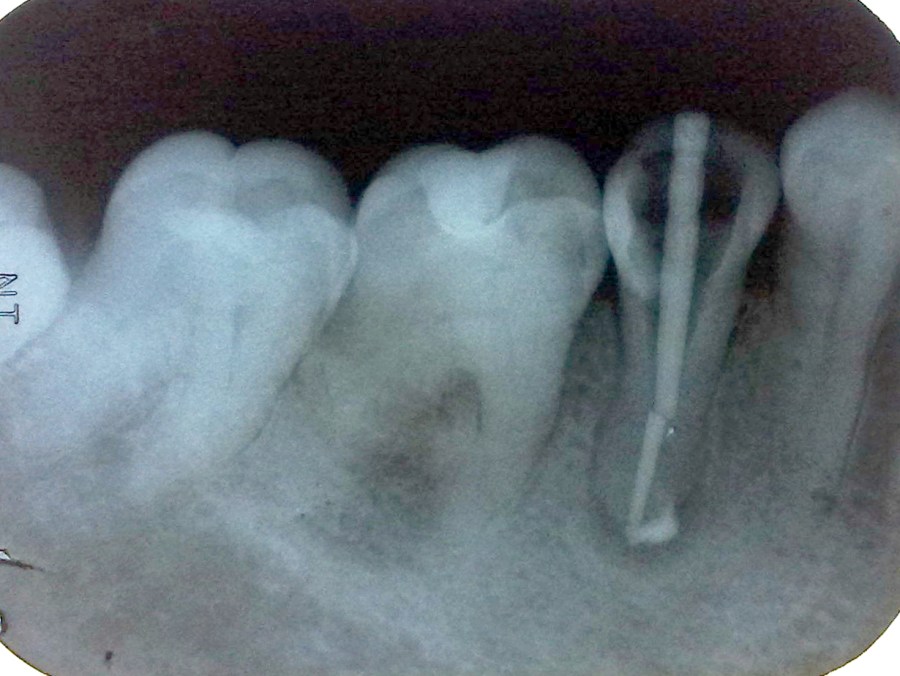

Endodontic treatment on lower right first molar with radix entomolaris